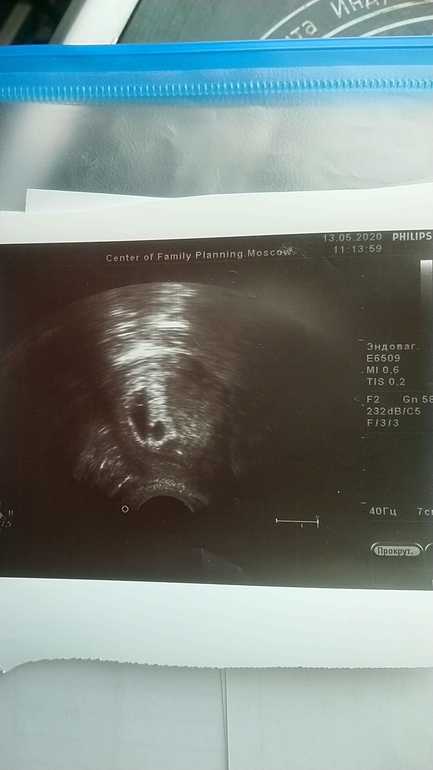

Замершая и внематочная беременностьПривет, девочки. На понедельник назначена чистка. Анэмбриония. В понед. будет срок 7н5д. В 6 недель ПЯ было пустое, в 7н по описанию узи размер ПЯ 19мм и желт. мешочек 4мм, ждать уже нечего, да и к тому же ПЯ с перегородкой(это тоже не норма, как сказал врач). Записали на чистку в самом ЦПСиР(Москва). Смущает, что по умолчанию делали бы простую чистку, когда я спросила про вакуум, то начали узнавать и сказали, что делают, но нужно предупредить обязательно. Перед самой чисткой узи там не делают, поэтому Ре сказала заскочить к ней на узи, для успокоения совести(но надежды, как она сказала нет "совсем" ) Теперь у меня сомнения: точно ли там хорошо делают? Очень боюсь последствий, вдруг в итоге сделают простую чистку или вакуум плохо 🙈Отзывов что-то не нашла. Страхов куча. У меня вопрос: кто делал вакуум(особенно по омс) ? какие последствия у Вас были? как долго восстанавливались? через сколько потом пошли снова в крио(не хочется затягивать). P.S. был крио на згт, подсаживали 1эмбр. 4АВ. Про МА Ре как-то вскользь упоминула, и то только когда я спросила. Сказала ну да, в принципе тоже можно и всё на этом. В общем любые отзывы будут полезны. Спасибочки.